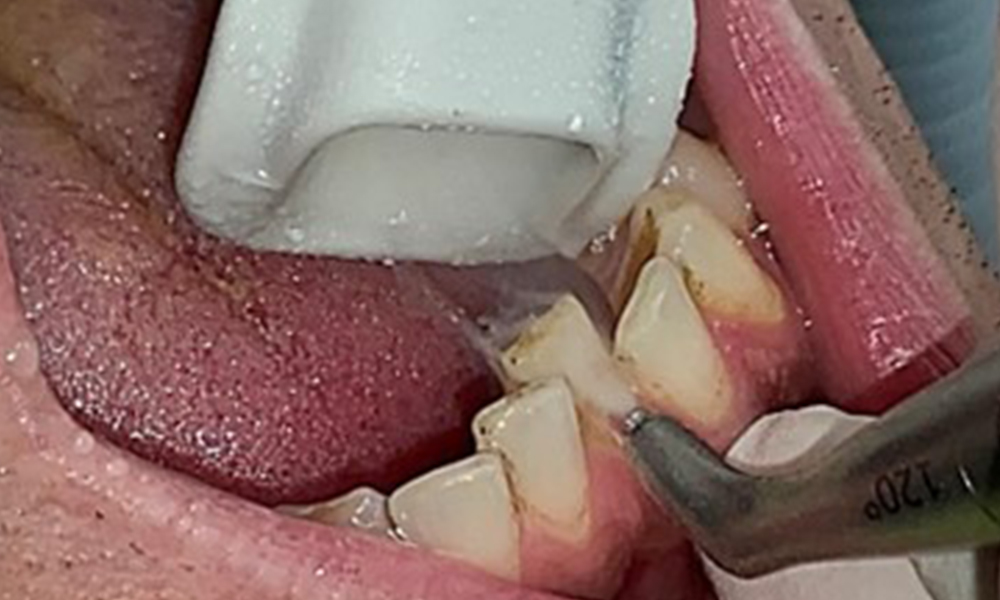

The objective would be to control disease risk by removing supragingival and subgingival biofilm. The instruments can be selected based on patient needs. First, calculus and any concretions must be removed using ultrasonic and/or manual instruments (Fig. 10).

Use of a piezo-driven ultrasonic device in the lingual area near 36

Fig. 10 Use of a piezo-driven ultrasonic device in the lingual area near 36 (Proxeo Ultra, W&H, shown here), © Dr R. Krapf